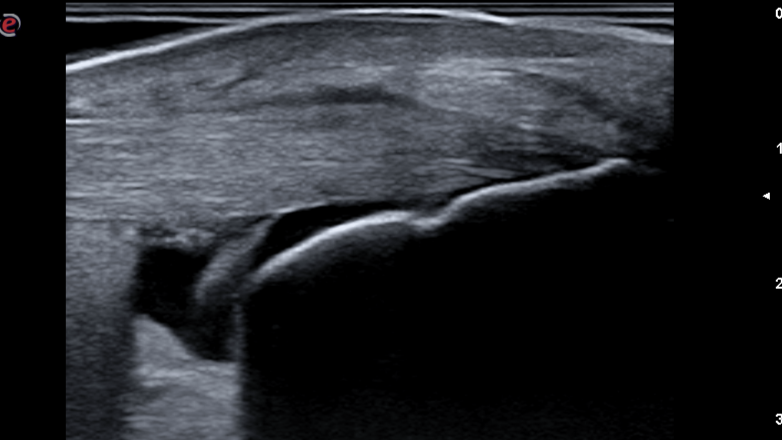

Ecografía del Tobillo donde se muestra bursitis retrocalcanea

Bursitis Retrocalcánea